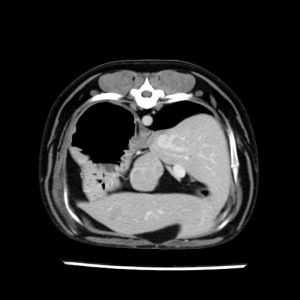

La lesione focale epatica , la ceus,la Tac e il chirurgo .